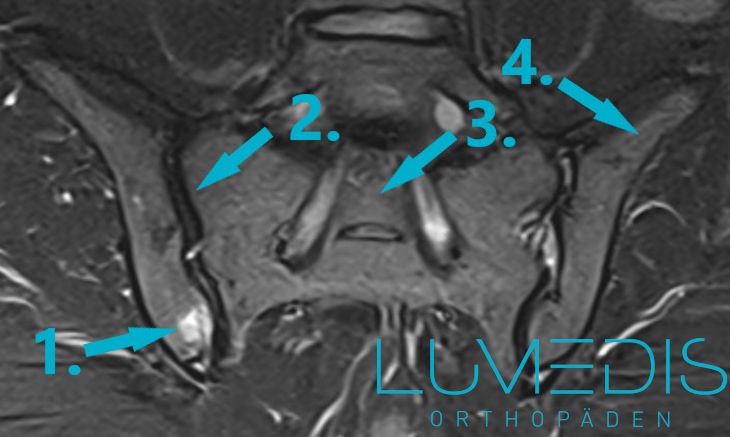

Bild einer Sakroiliitis im MRT

Ein MRT vom ISG wird immer dann durchgeführt, wenn die Ursache der Beschwerden nicht ersichtlich ist und die Krankenbefragung, die körperliche Untersuchung sowie Röntgenuntersuchung keinen Aufschluss darüber bringen konnte, was der Auslöser für die Beschwerden ist.

Weiterhin, wenn man vermutet, dass Muskel, Bänder oder Sehnenverletzungen die Beschwerden auslösen. Das MRT vom Iliosakralgelenk ist eine strahlungsfreie, diagnostische Maßnahme, bei der durch ein aufgebautes Magnetfeld und ein danach mittels eines Computers errechnete Bild eine Darstellung von Knochen, Bänder, Sehnen, Gefäße und Nerven erfolgen kann.

Eine Sakroiliitis lässt sich sehr gut im MRT vom Becken darstellen.

MRT einer Sacroiliitis rechts